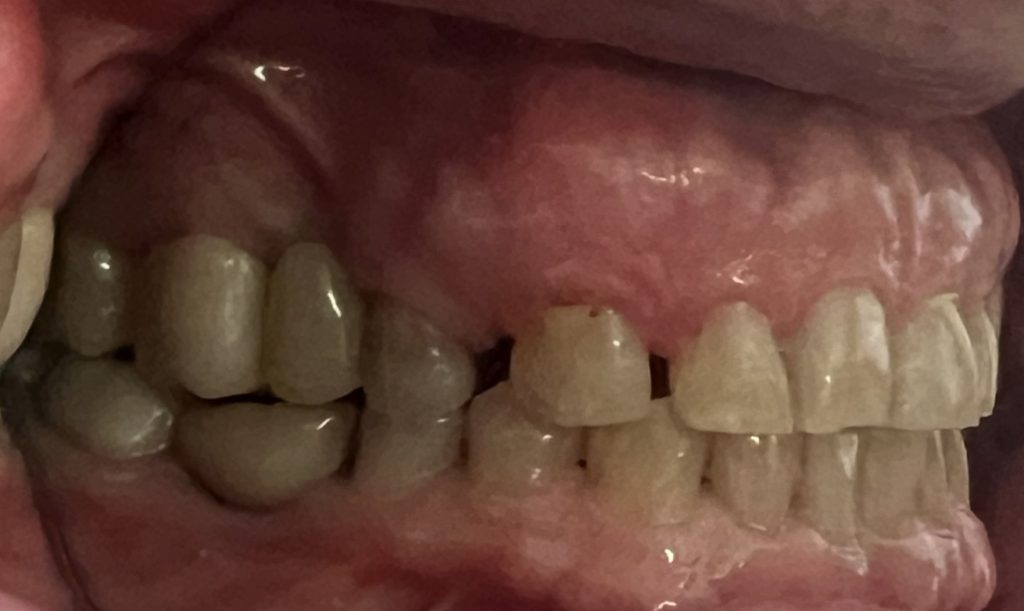

It does not matter whether teeth were lost through accident, disease or caries, dental implants are an excellent tooth replacement for many patients.

- A single tooth is missing – Crowns

- Several teeth are missing – Bridges